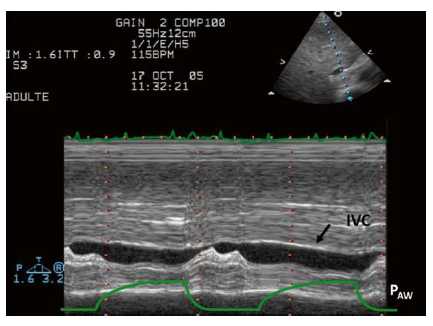

Você recebe na UTI um paciente, em ventilação mecânica invasiva, oriundo da sala

de emergência com diagnóstico de sepse respiratória. Ele apresenta pressão arterial média de 65

mmHg (recebendo noradrenalina em dose 0,3 mg/Kg/min) e apresenta enchimento capilar de 6

segundos. Realizada ultrassonografia torácica, abaixo representada:

Com base nessas informações, qual a conduta mais adequada a ser tomada em relação ao paciente?